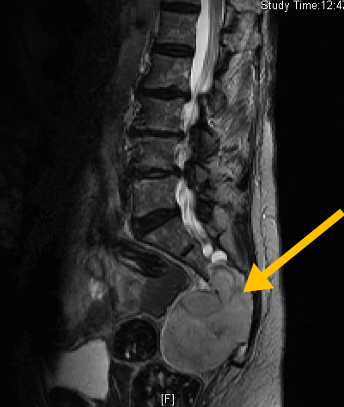

• • The work-up for Chordoma often consists of a physical examination, X-ray, MRI, and CT scans. Bone scan is used to detect spread to other bones. CT chest, abdomen and pelvis evaluates spread to lungs and liver or other organs. The diagnosis is often confirmed with a biopsy, which samples the tumor for further analysis.

Radiographic imaging is used to help form a diagnosis of Chordoma. These include X-Ray, MRI, CT and Bone Scans

An example of an X-ray is shown.